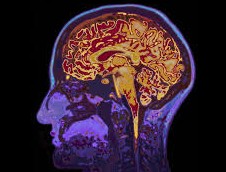

Le cerveau lui-même ne possède pas de récepteurs de la douleur, mais plusieurs mécanismes expliquent pourquoi les tumeurs cérébrales provoquent des maux de tête. Le plus simple est qu'une tumeur peut augmenter la pression intracrânienne (pression à l'intérieur du crâne) et provoquer un étirement de la dure-mère, la membrane qui recouvre le cerveau et la moelle épinière. Cela peut être douloureux, car la dure-mère est dotée de terminaisons nerveuses sensorielles.

En outre, les tumeurs peuvent parfois apparaître à des endroits qui bloquent la circulation normale du liquide céphalorachidien, le liquide créé dans le cerveau qui recouvre et amortit le cerveau et la moelle épinière. L’augmentation du liquide peut également augmenter la pression intracrânienne .

Certaines personnes émettent également l’hypothèse que l’étirement des vaisseaux sanguins par une tumeur pourrait être perçu comme douloureux, ajoutant : Il est également possible que certaines tumeurs libèrent des protéines inflammatoires (cytokines) qui peuvent contribuer aux maux de tête.

Deux principaux symptômes peuvent révéler la présence d’une tumeur cérébrale. Le premier est l’apparition de maux de tête inhabituels (céphalées), dus au volume de la tumeur qui augmente la pression dans le crâne, pouvant aller jusqu’à une hypertension intracrânienne accompagnée de nausées et de vomissements. Cette hypertension dite « intracrânienne » est due à la combinaison de plusieurs causes : la réaction inflammatoire autour de la tumeur (un gonflement appelé « œdème »), la compression provoquée par la tumeur lorsqu’elle grossit, et une mauvaise circulation du liquide céphalo-rachidien dans le crâne.